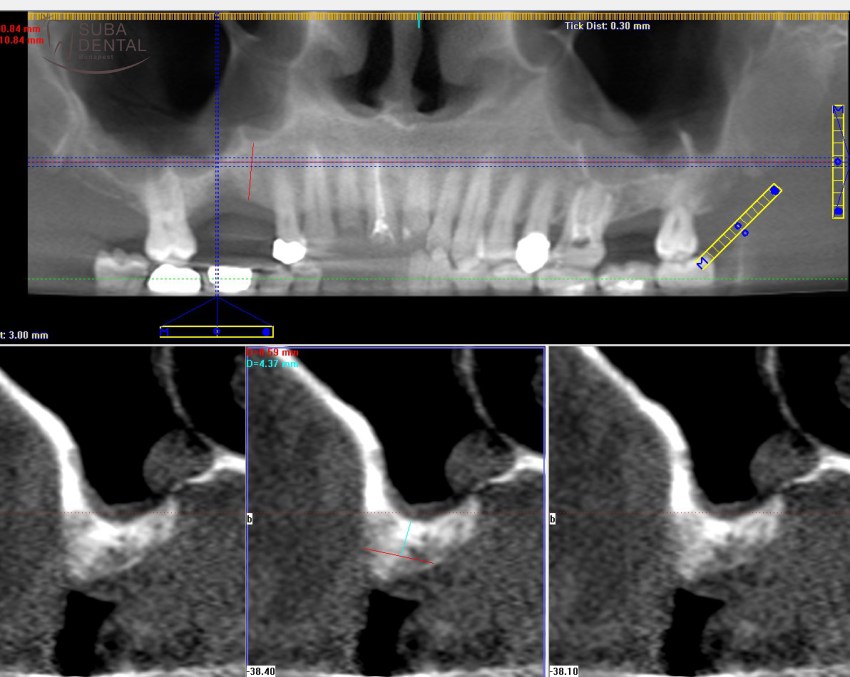

Often bone width at the site of the upper molars is sufficient but bone height is inadequate. In such instances a so-called sinus lift is required. Sinus lift is a special maxillofacial surgery performed using the PRF technique by cutting a window into the wall of the maxillary sinus with a piezo (Piezo Med, W&H) and lifting the Schneiderian membrane by introducing bone graft material into the maxillary sinus in order to lift the height of the bone. If bone width is sufficient with bone height exceeding 4 mm, a sinus lift and implant surgery can be performed simultaneously since a 4 mm high bone can support an implant and offer good primary stability until the bone graft material integrates and new bone forms in the maxillary sinus around the implant. A minimum of 6 months’ healing time is required before installing the permanent tooth restoration. If bone width is sufficient but bone less is less than 4 mm, a so-called 2-step sinus lift is necessary. This means that in the first session only a sinus lift (bone graft) is performed to fill up the maxillary sinus with bone graft material, and the implants can only be installed after 6 months’ healing time. Once the implants are mounted, another 4 to 6 months are required before the permanent replacement tooth can be cemented/screwed in place.

The CT scan revealed that the bone in the upper jaw bone did not heal quite as expected. Bone height was inadequate but bone width was perfectly suited for implants to be mounted. In such cases a bone graft surgery, that is, a sinus lift is required to increase bone height in order to make the installation of implants possible.

After 3 months of healing the CT scan revealed that bone height was inadequate on both sides, and a sinus lift was necessary, which could not be performed in the same sitting with implant surgery due to inadequate bone height. In the second sitting bone graft was performed in the upper arch and the lower implants were installed (2 per quadrant).